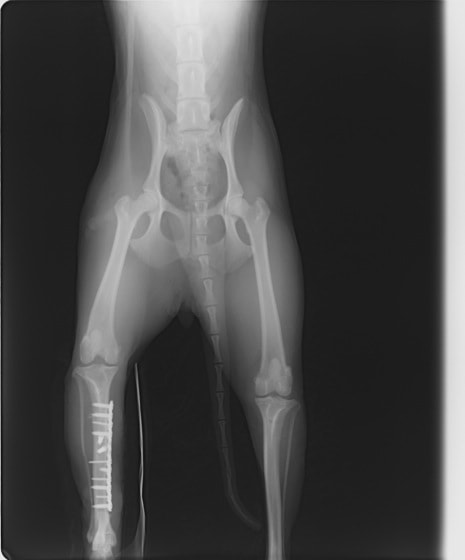

脛骨骨折 : 症例1 | 症例2 | 症例3 | 症例4 | 症例5

症例3:キルシュナーワイヤーのピンニングによる整復

ペルシャ猫 11ヶ月齢 雄

他院にて左大腿骨遠位の成長板骨折(salter-harrisⅠ型)が認められており、治療相談を目的として来院。当院にて、キルシュナーワイヤーを用いたピンニングにより骨折部位の整復を行いました。術後の経過は良好で、現在も経過観察中です。

術前レントゲン

術後レントゲン